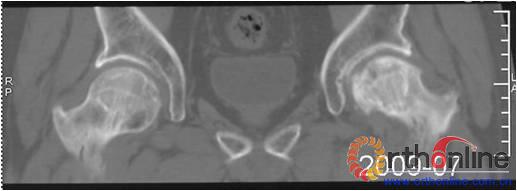

(一)    解剖学研究。引用HerringLegg-Perthes病的三柱概念,将股骨头分为外、中、内三柱,划定外侧柱占股骨头宽度的30%、中央柱占40%、内侧柱占30%。(图1

1 股骨头冠状面三柱结构:外侧柱占30%,中央柱占40%,内侧柱占30%

Fig. 1 The three pillars of coronal section of the femoral head: lateral  30%, central  40%, medial   30%